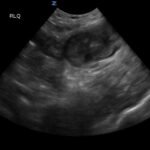

Small bowel diverticulitis is an uncommon subset of acute diverticulitis and can mimic many other intra-abdominal processes. As a result, imaging modalities such as ultrasound and computed tomography (CT) scan are especially important for timely recognition of diverticulitis and can expedite diagnosis and treatment and reduce complications. In the case described in this report, an 81-year-old male with history of esophageal cancer and recurrent diverticulitis with history of multiple bowel resections presented to the emergency department (ED) with right lower quadrant abdominal pain and constipation. Findings on ultrasound were suggestive of diverticulitis, and findings on CT of the abdomen and pelvis showed ileitis with phlegmon and micro-abscess suspicious for small bowel diverticulitis. ED providers should familiarize themselves with ultrasound findings of diverticulitis and be aware that diverticulitis can also present in the small bowel. Treatment of small bowel diverticulitis is similar to colonic diverticulitis.